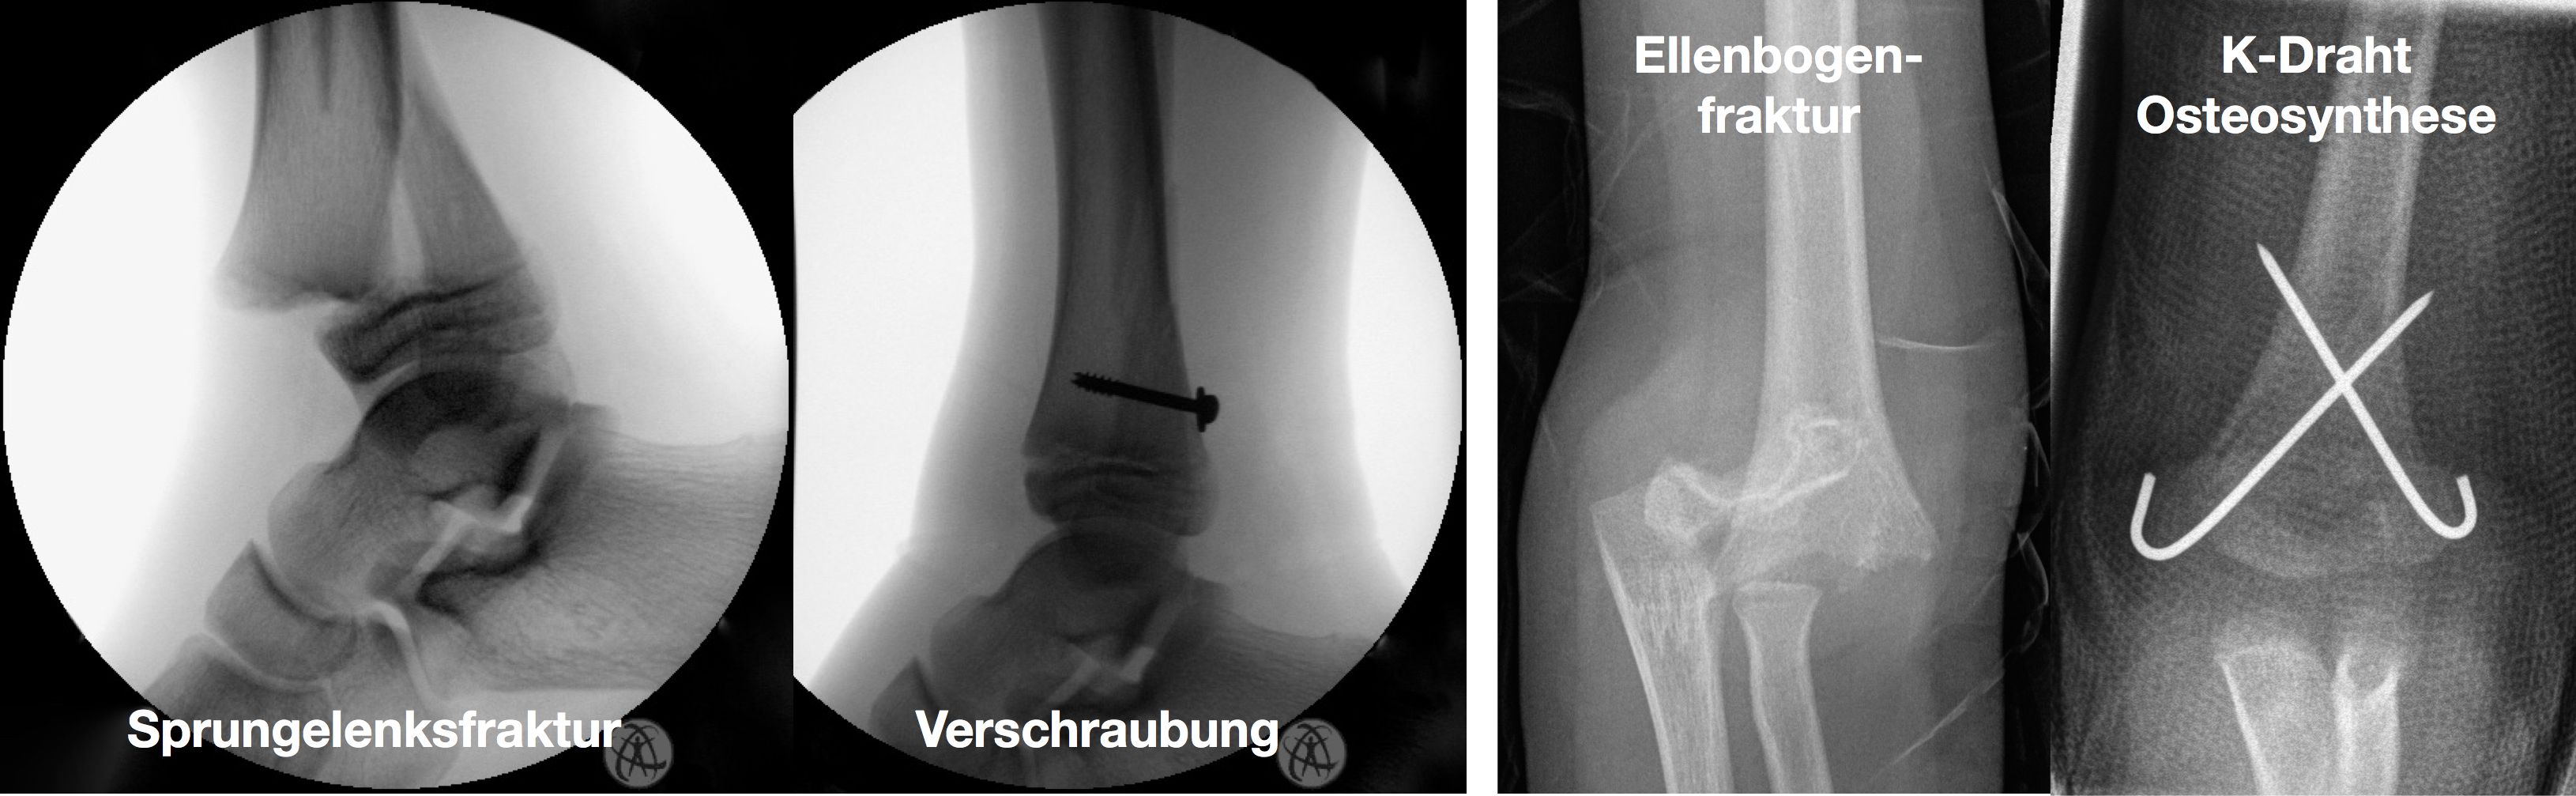

Kirschner-Draht-Osteosynthese

Andere Verfahren der operativen Frakturversorgung im Kindesalter sind die Kirschner-Draht-Osteosynthese, die Verschraubung, der Fixateur und die Plattenosteosynthese. Metallentfernungen werden ambulant durchgeführt, Nachuntersuchungen zum Ausschluss etwaiger Wachstumsstörungen erfolgen in unserer Frakturensprechstunde.